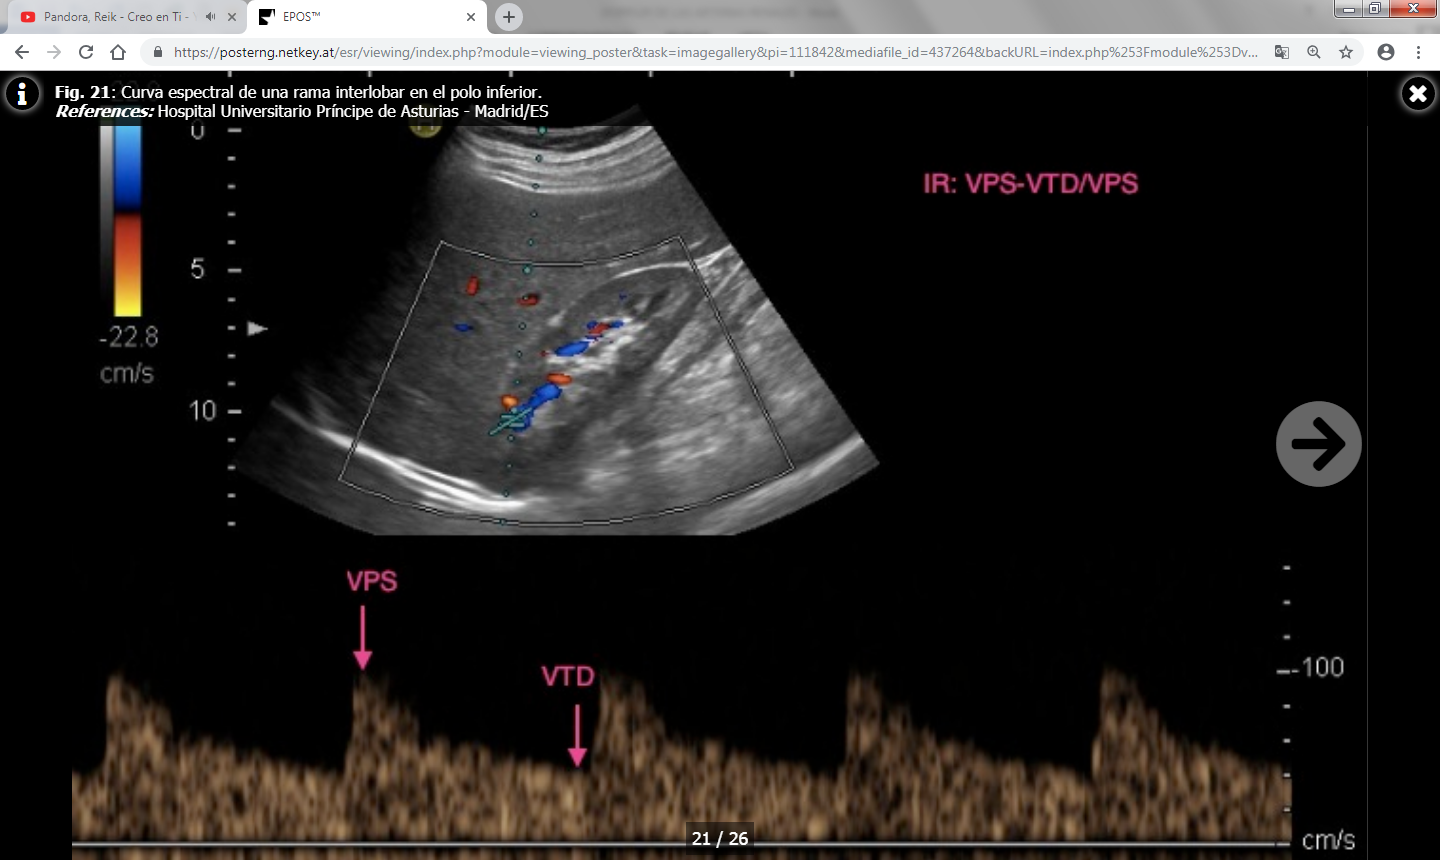

- Índice de resistencia (IR) : Es el resultado del cociente VPS – VTD / VPS (siendo VPS la velocidad picosistólica y VTD la velocidad al final de la diástole). Se debe calcular una media con las distintas medidas obtenidas en cada riñón y valorar si existen diferencias entre un riñón y el contralateral. Lo normal es que el índice de resistencia esté entre 0.6-0.7 y que la diferencia entre ambos riñones sea menor del 5% (ó 0.05). Un aumento de la velocidad telediastólica mayor de 150 cm/s en un paciente con IR intrarrenal menor de 0.7 es altamente sospechoso de estenosis mayor del 80%.